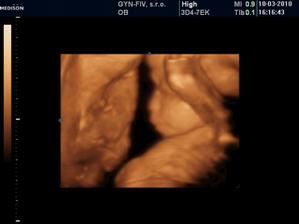

Ako rýchlo rastieme v brušinku 🙂

tatianka ďakujeme veľmi pekne 🙂 aj my sa z nich vytešujeme, kým je malinká v brušku a nevidím ju naživo